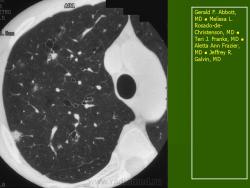

Поражение легочной ткани (рис. 22) свойственно любому возрасту. Часто больные имеют общие симптомы — лихорадку, слабость, реже — кашель, одышку, боли в грудной клетке. На рентгенограммах отмечается деформация и усиление легочного рисунка и микроузловые инфильтративные тени. Поражение костного мозга (с наличием клеток Лангерганса) сопровождается цитопенией периферической крови.

Рис. 22. Поражение легких при Лангер-гансово-клеточном гистиоцитозе.